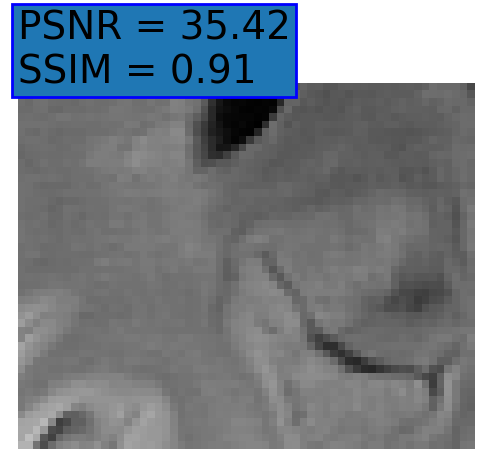

Figure 3: Reconstructions results. Rows 1 and 3: Examples of comparing the ground truth (GT) fully sampled image to the reconstructed images obtained by the three models (1-3), NPB-REC, baseline, E2E-VarNet trained with Dropout, and the NPB-REC std. map at accelerations R=4𝑅4R=4, R=8𝑅8R=8, respectively. Rows 2 and 4: The corresponding annotated ROIS of Nonspecific white matter lesions.

Fig. 3 presents examples of reconstruction results obtained by (1) our NPB-REC approach, (2) the baseline, and (3) Monte Carlo Dropout, for equispaced masks with two different acceleration rates R=4𝑅4R=4 and R=8𝑅8R=8. The reconstructed images predicted by the three models are smoother than the reference image. This is due to the fact that all the models were trained with SSIM loss, which tends to produce overly smooth reconstructions while preserving the diagnostic content and the anatomical features Sriram et al. (2020a). These images can be enhanced by dithering the image by adding a small amount of random Gaussian noise to produce a more textured reconstruction, as proposed in Sriram et al. (2020b).

Table 1 presents the mean PSNR and SSIM metrics, calculated over the whole inference set, for the three models. Our NPB-REC approach achieved significant improvements over the other methods in terms of PSNR and SSIM (Wilcoxon signed-rank test, pmuch-less-than\ll1e-4, except for SSIM values in line W, R=4𝑅4R=4 where they are roughly the same for NPB-REC and Baseline). The improvement in the reconstruction performance can be noted both quantitatively from the metrics, especially for masks with acceleration rate R=8𝑅8R=8, and qualitatively via the images of annotations, where our results show less smoothness than those obtained by Dropout.